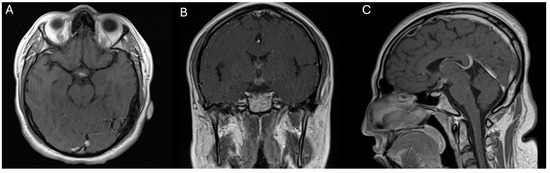

Figure 3. Scans illustrating the 3-month follow-up MRI after gamma knife radiosurgery (GKRS) and revealing a significant reduction in the size of the hypothalamic lesion. The images show minimal contrast enhancement compared to previous imaging studies. The lesion’s volume decreased to approximately 2.19 cm3, as visualized in the axial (A), coronal (B), and sagittal (C) MRI sequences.

At the three-month follow-up following GKRS, the patient exhibited substantial clinical improvement (Figure 2). He no longer demonstrated symptoms of encephalopathy or lethargy, and his mental status had returned to “normal.” Furthermore, the patient’s neurological examination was unremarkable, and repeat MRI imaging demonstrated a significant decrease in tumor volume. Desmopressin therapy maintained satisfactory control of diabetes insipidus, and no new neurological deficits were identified (Figure 3). The efficacy of radiosurgery as a minimally invasive treatment option for hypothalamic gliomas is emphasized by these results, particularly in situations where conventional surgery demonstrates significant risks.